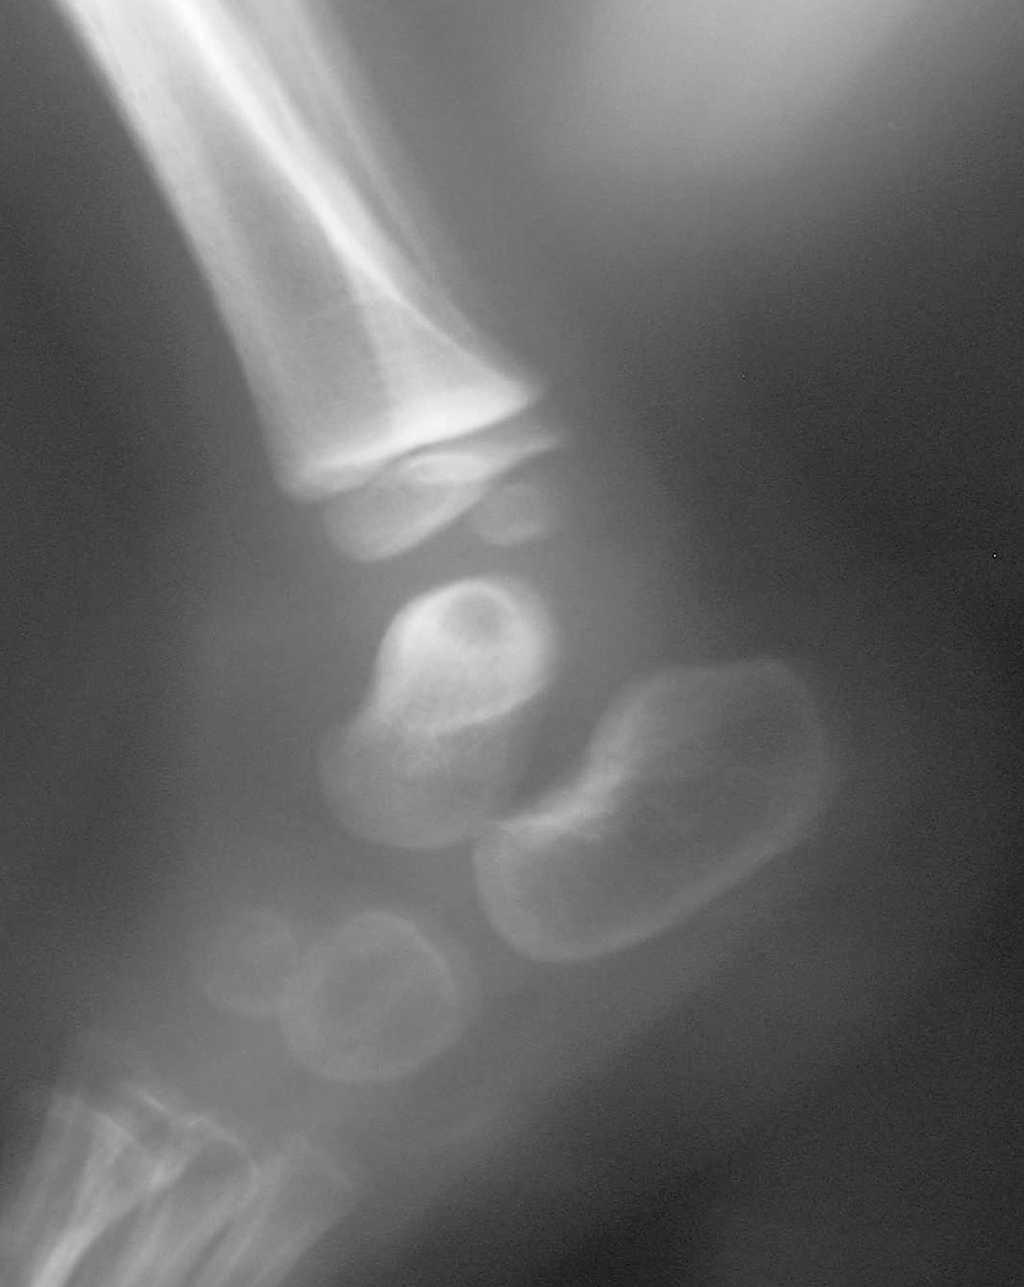

El número total de pacientes fue 35. Se agruparon en: a) artritis séptica segura, casos con confirmación bacteriológica u osteoartritis y b) artritis séptica probable, aquellos otros sin confirmación bacteriológica con buena respuesta a antibióticos. El grupo de artritis séptica segura estuvo constituido por 7 niños, tres con cultivos positivos en líquido articular (dos por Staphylococcus aureus y uno por Kingella kingae) y uno en hemocultivo por Streptococcus pneumoniae y 3 niños con osteoartritis demostrada por radiología convencional un caso (fig. 1) y por gammagrafía ósea con tecnecio99 en dos. El grupo de artritis séptica probable lo constituyeron 28 pacientes.

Figura 1. Osteomielitis del astrágalo.